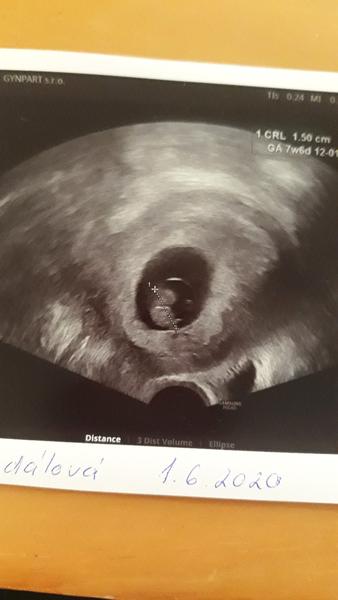

Tak mám za sebou kontrolu a úplně se mi ulevilo. Mimco je zdravý, krásně mu bije srdíčko a vypadá že to bude bojovnice nebo bojovnik🥰 hned jak jsem přišla tak mi říkala že je možný že díky tomu krvácení tam třeba mimco už ani nebude a pak udělala ultrazvuk a řekla "Tyjo tak to jsem nečekala ani já 😂" prej za ty 2 týdny udělal obrovský pokrok 🥰